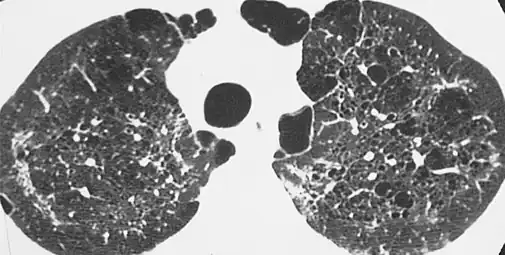

The diagnosis can be confirmed by the characteristic appearance of the chest X-ray and an arterial oxygen level (PaO2) that is strikingly lower than would be expected from symptoms. Gallium 67 scans are also useful in the diagnosis. They are abnormal in about 90% of cases and are often positive before the chest X-ray becomes abnormal. Chest X-ray typically shows widespread pulmonary infiltrates. CT scan may show pulmonary cysts (not to be confused with the cyst-forms of the pathogen).

High-resolution computed tomography (HRCT) showing ground-glass attenuation with a geographic or mosaic distribution.[6]

HRCT of cysts of pneumocystis pneumonia. These are usually multiple and bilateral, but range in size, shape and distribution.[6]